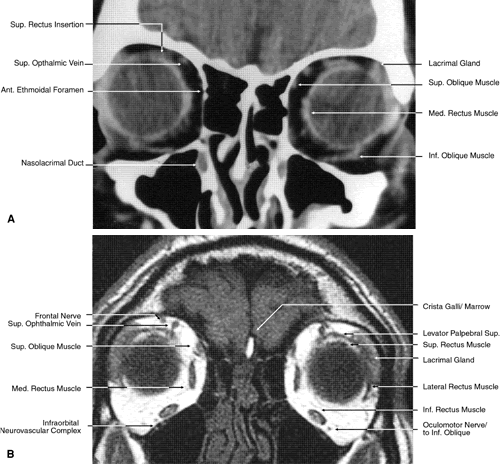

Fig. 17. Coronal images through anterior orbit. A. Computed tomography scan. B. T1-weighted magnetic resonance imaging.

Fig. 18. Coronal images through midglobe. A. Computed tomography scan. B. T1-weighted magnetic resonance imaging.

Fig. 19. Coronal images through midorbit posterior to the globe. A. Computed tomography scan.B. T1-weighted magnetic resonance imaging.

Fig. 20. Coronal images through orbital apex. A. Computed tomography scan. B. T1-weighted magnetic resonance imaging. C. Anatomic section of a cadaver head at the level of the orbital apex.

Fig. 21. Coronal images through optic canal. A. Computed tomography scan. B. T1-weighted magnetic resonance imaging.

Fig. 22. Axial images at the level of inferior orbit. A. Computed tomography scan. B. T1-weighted magnetic resonance imaging.

Fig. 23. Axial images at the level of midorbit. A. Computed tomography scan. B. T1-weighted magnetic resonance imaging.

Fig. 24. Axial images at the level of superior orbit. A. Computed tomography scan. B. T1-weighted magnetic resonance imaging.

Fig. 25. Axial images at the level of tendon of the superior oblique. A. Computed tomography scan. B. T1-weighted magnetic resonance imaging.

Fig. 26. T1-weighted magnetic resonance imaging; sagittal image through optic nerve.

The globe is shown in Figure 12. The orbit and periorbital structures are shown in Figures 13 through 16, and the optic canal is shown in Figures 17 through 26. The cavernous sinus and optic chiasm are shown in Figures 27 and 28, and the posterior visual pathway and cranial nerves are shown in Figures 29 through 33.